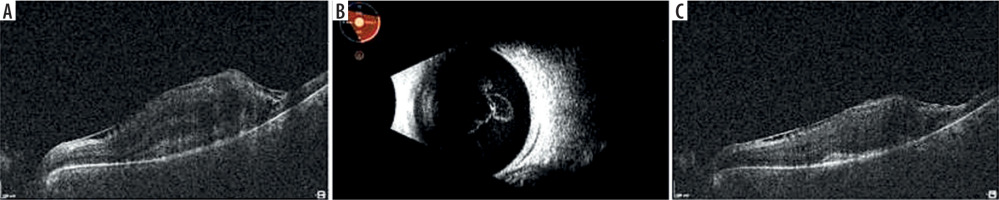

A 54-year-old woman was hospitalized due to necrotic retinitis of her left eye (LE). She noticed floaters and decrease of visual acuity (VA) one month earlier with concomitant general weakness. As she experienced the similar floaters in her right eye (RE) about one year earlier with its spontaneous resolution, she did not initially seek medical attention. Her medical history was notable for peripheral spondyloarthropathy (HLA-B27+) for 10 years. The disease had been controlled by oral MTX 25 mg once weekly for 3 years, methylprednisolone 3 mg daily for 10 years, and nonsteroidal anti-inflammatory drugs (NSAIDs). She also suffered from post-steroidal diabetes and osteoporosis. At admission her VA (Snellen) was 1.0 and 0.4 for RE and LE, respectively. Right eye showed atrophic perifoveal scar (Figure 1A) and LE mild anterior segment inflammation. Fundus eye examination found vitreous inflammatory opacities and large nonhomogeneous inflammatory lesion with signs of diffuse arteritis (Figure 1B). Fluorescein angiography (FA) showed the hypofluorescence area with hyperfluorescent center (Figure 1C). Serology testing was notable for toxoplasma (IgG > 200, positive if > 3.0, and IgM 0,48, negative if < 0.5), cytomegalovirus (CMV; IgG 177, positive if > 6.0, IgM not reactive) and herpes zoster virus (HZV; IgG 448.47, positive if > 110, IgM negative). Syphilis, HIV, and herpes virus type 1 and 2 were negative. Blood count revealed slightly decreased levels of monocytes and lymphocytes. Methotrexate treatment was discontinued due to immunosuppression. Oral trimethoprim/sulfamethoxazole (TS) twice a day and clindamycin 1 mg intravitreally twice with an interval of 5 days were given. Additionally, oral acyclovir 800 mg 5 times per day was prescribed. In the following 10 days of hospitalization, the inflammation decreased and VA increased to 0.5 (Figure 1D). Patient was discharged from the hospital on methylpredniso-lone and TS. At the 3-week follow-up, massive retinal neovascularization was found with persistent retinal inflammation (Figure 2A–C). Two complementary intravitreal injections of clindamycin resulted in rapid improvement. The signs of arteritis almost disappeared, and panretinal photocoagulation was urgently done. Prophylactic doses of TS (1 tablet every 3 days) were prescribed. On follow-up, VA was gradually decreasing to 0.02 due to progressive macular edema and membrane (Figure 3A). At the 8-month follow-up visit spontaneous posterior vitreous detachment (PVD) with concomitant vitreous hemorrhage occurred and VA was hand movements (Figure 3B). Anti-VEGFs (aflibercept twice and faricimab once) were injected in case of macular edema aggravation. At the 18-month follow-up visit VA was 0.1 (Figure 3C).

Figure 1

A) Fundus photography one year before the event with atrophic scar in the macula of RE and Weiss ring just above optic disc. B) Fundus photography at presentation with arcuate snow-white, fluffy lesion and diffuse arteritis. C) Fluorescein angiography of late phase shows intensive hyperfluorescence in the center and large mild hyperfluorescence around, reinforced at the borders. D) Less inflamed lesion 10 days later before discharge